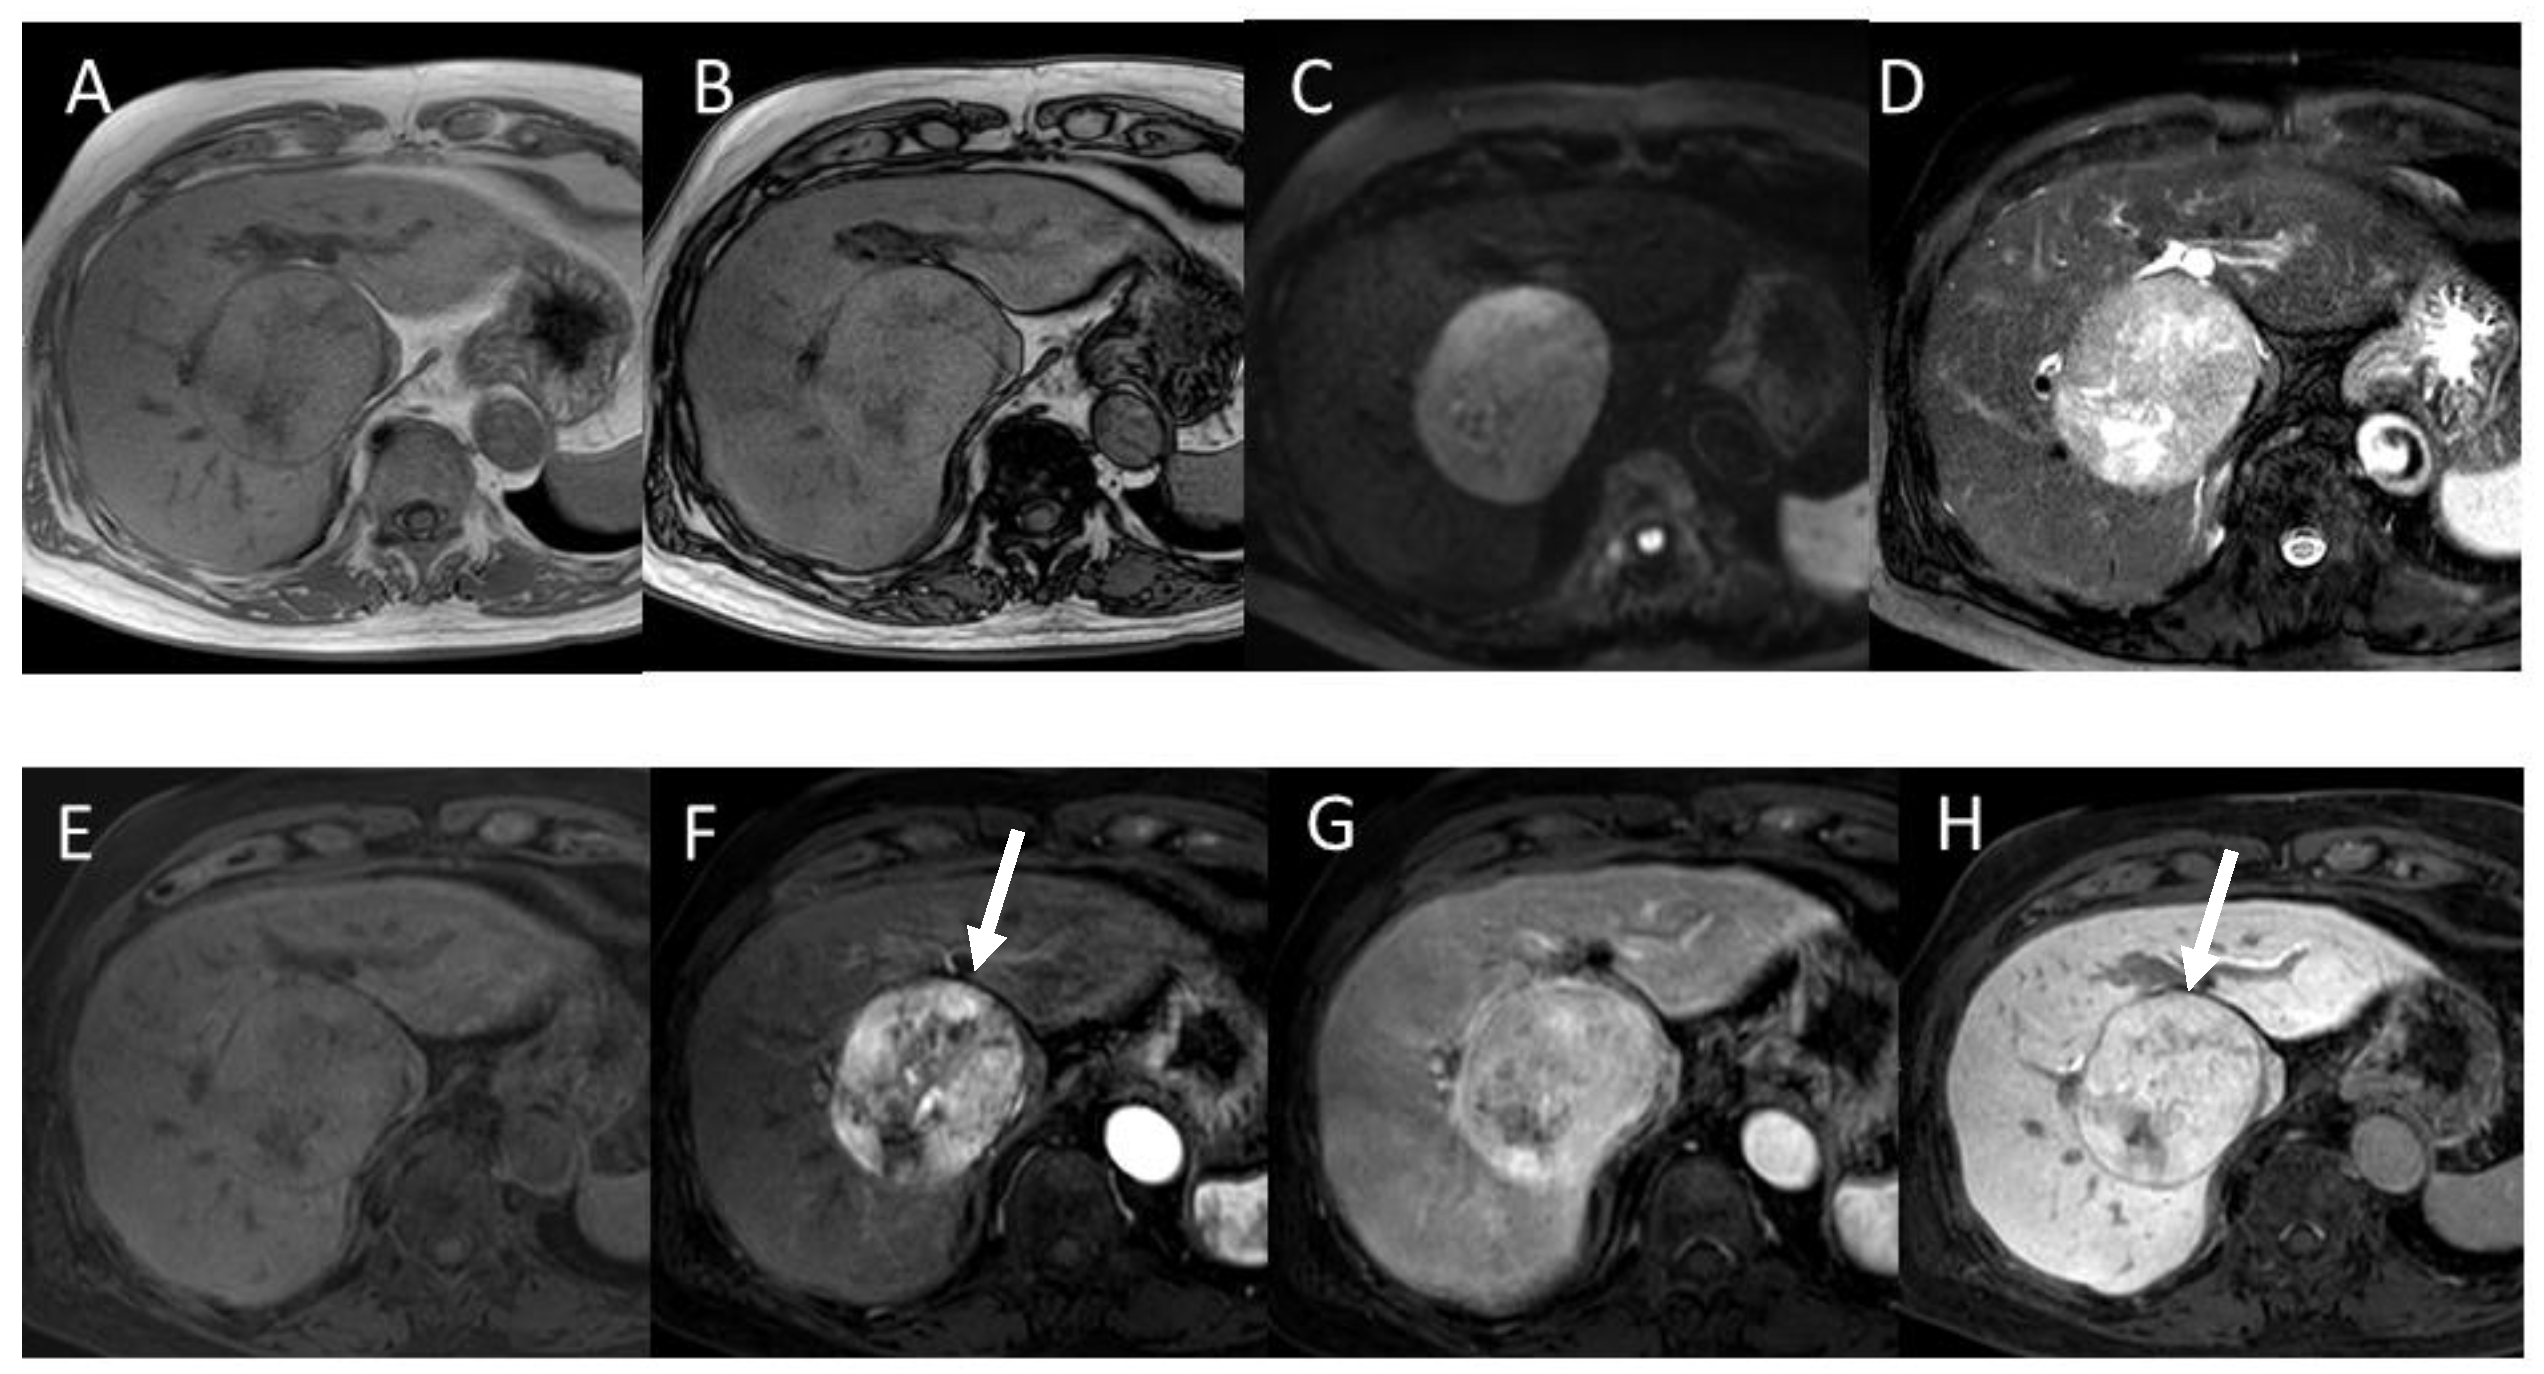

4.3. Well-Differentiated Hepatocellular Carcinoma (Well-HCC)

4.4. Moderately Differentiated Hepatocellular Carcinoma (Moderately HCC)

4.5. Poorly Differentiated Hepatocellular Carcinoma (Poorly HCC)